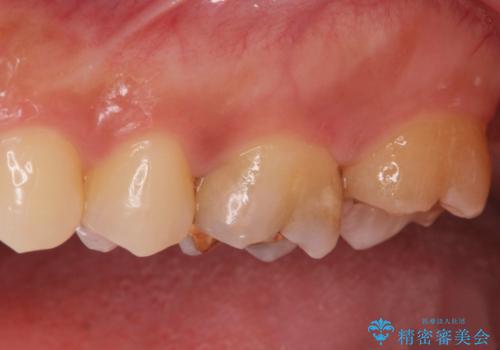

金の詰め物の中にある虫歯を除去してセラミック治療

- 金の詰め物の中が黒く透けていて虫歯があるので拡大鏡下で外し、虫歯がない事を確認した後、被せ物で治療しました。

一番奥の歯は古い樹脂の治療の後がありましたのでセラミックの詰め物で治療しました。